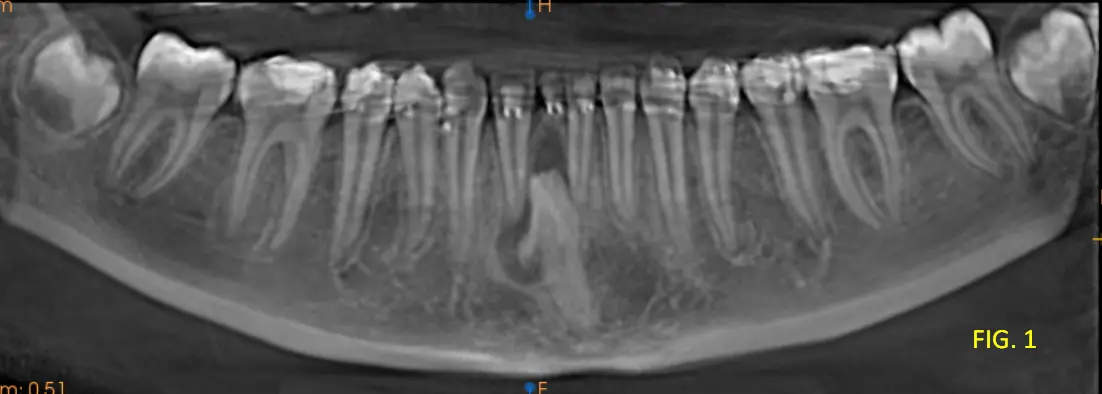

Paciente con ortodoncia, poco colaborativo (se movia) y que ademas presentaba ortodoncia, lo que dificulta obtener una imagen de buena calidad (Imagen 3D). Durante la evaluación de la tomografía se visualiza una pieza dentaria no erupcionada (PD 41 ) que presentaba en boca todavia su PD temporaria 81, esa pieza dentaria presentaba un saco dentinario aumentado de tamañao lo que nos lleva al diagnóstivo presuntivo de un Quiste Dentígero, pero además se observa que en el mismo se observa un pequeño elemento radiopaco asociada a dicha lesión, se identifica una imagen hiperdensa, de morfología irregular, compatible con un quiste dentario organizado, correspondiente a un odontoma (ver cortes coronal, axial, transaxial, Fig 1, 2 y 3).

Las características imagenológicas nombradas son compatibles con Quiste dentígero de Pd 41 asociado a un odontoma compuesto.